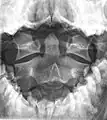

A fracture of the base of the dens as seen on plain X-ray

A fracture of the base of the dens as seen on CT